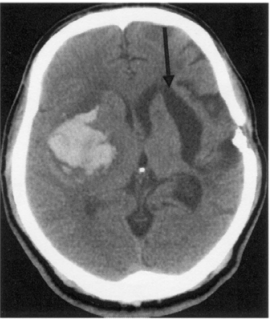

73 一位 54 歲男性,因左側突然半身無力來做 CT,CT 影像如下圖所示,發現右側基底核有一血塊,同 時也看到左側基底核有一病灶(箭頭所指),左側頭蓋骨有開過刀。經追問家屬,病患右側肢體無 力已 5 年,此左側基底核病灶是:

(A) A cyst of brain tissue (B) An arachnoid cyst from Sylvian fissure (C) An old intracerebral hematoma (D) An old infarction